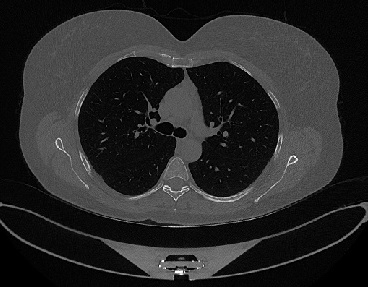

It should be mentioned that for explainability purposes [7, 8, 9], an anchor set was generated for the COV19-CT-DB database [5]. This included 11 anchors, each representing a respective 3-D CT scan obtained through an appropriate clustering procedure. Figure 2 shows a series of slices from a COVID-19 case, whereas Figure 3 shows a series of slices from a non COVID-19 case.